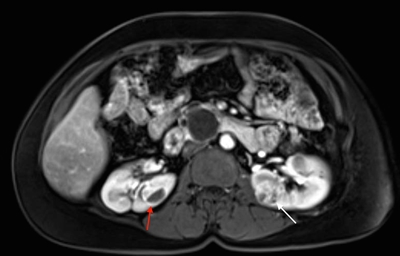

More than 55% of individuals with von Hippel-Lindau disease (VHL) only develop multiple renal cell cysts. VHL-associated renal cell carcinomas (RCCs) are characteristically multifocal and bilateral. These RCCs present as masses with both cystic and solid characteristics.[1] In VHL, the cumulative risk of RCC was reported to be 24% to 45%. RCCs smaller than 3 cm tend to be low-grade (Fuhrman nuclear grade 2) and minimally invasive.[2] However, their growth rate varies widely.[3] An investigation of 228 renal lesions in 28 patients who were followed for at least 1 year showed that transition from a simple cyst to a solid lesion was infrequent.[1] Complex cystic and solid lesions contained neoplastic tissue that was uniformly enlarged. These data may be used to predict the progression of renal lesions (from benign to malignant) in patients with VHL. Figure 1 depicts bilateral renal tumors in a patient with VHL.

Axial view of an individual's midsection showing tumors in both kidneys. The left kidney has a tumor with a dark cystic component and the right kidney has a predominantly solid tumor.

Figure 1. von Hippel-Lindau disease–associated renal cell cancers are characteristically multifocal and bilateral and present as combined cystic and solid masses. The red arrow shows a lesion with a solid and cystic component, and the white arrow shows a predominantly solid lesion.